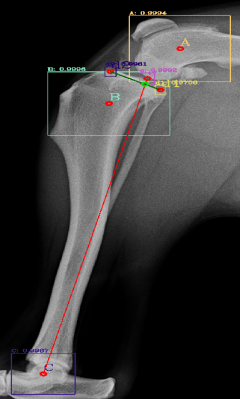

Most of the source dataset of over a thousand unique knee radiographs were distorted, had poor patient positioning, or were otherwise unfit for annotating. 250 of the original images were of sufficient quality to contribute to this effort. These images were set to have 6 different classes for training purposes, as mentioned and shown in Fig. 4. These were then trained using YOLOv3 [10] and the results of the predicted annotations are shown in Table I. From these predictions the centroids were extracted, which is then used to plot the FTL and MTPL. Then using the method mentioned in Section II, TPA is calculated. Examples of images, the region of interests detection and their respective TPA determination is shown in Fig. 6 and Table I:

| Image | YOLOv3 | YOLOv4-1 | YOLOv4-2 | YOLOv4-3 |

|---|---|---|---|---|

| 6(a) | 20.537° | 22.67° | 24.8° | 22.9° |

| 6(b) | 17.354° | 17.62° | 18.7° | 16.22° |

| 6(c) | 19.473° | 19.53° | 20.03° | 18.24° |

| 6(d) | 23.369° | 27.37° | 29.03° | 25.8° |

| 6(e) | 18.435° | 15.5° | 17.65° | 16.8° |

| 6(f) | 19.699° | 18.24° | 20.22° | 18.59° |

For comparison purposes the radiographs have been tested with YOLOv3, original YOLOv4 [12] and custom modifications of the YOLOv4 by changing the activation functions and the results are shown in Table II. The original version of YOLOv4 (addressed as YOLOv4-1 in Table II) combined the Mish, Linear and Leaky activation functions, the versions YOLOv4-2 and YOLOv4-3 used for the purpose of testing in this paper have combinations of Mish, Linear, Swish and Mish, Linear and Relu activation functions respectively. Similarly, comparison of the results that did not fall under the presumed normal range shown in Fig. 9, for the algorithm, are shown with variations in activation function in Table III. It can be seen here that these images, are giving TPA predictions similar to the original YOLOv3, i.e. outside of presumed range.